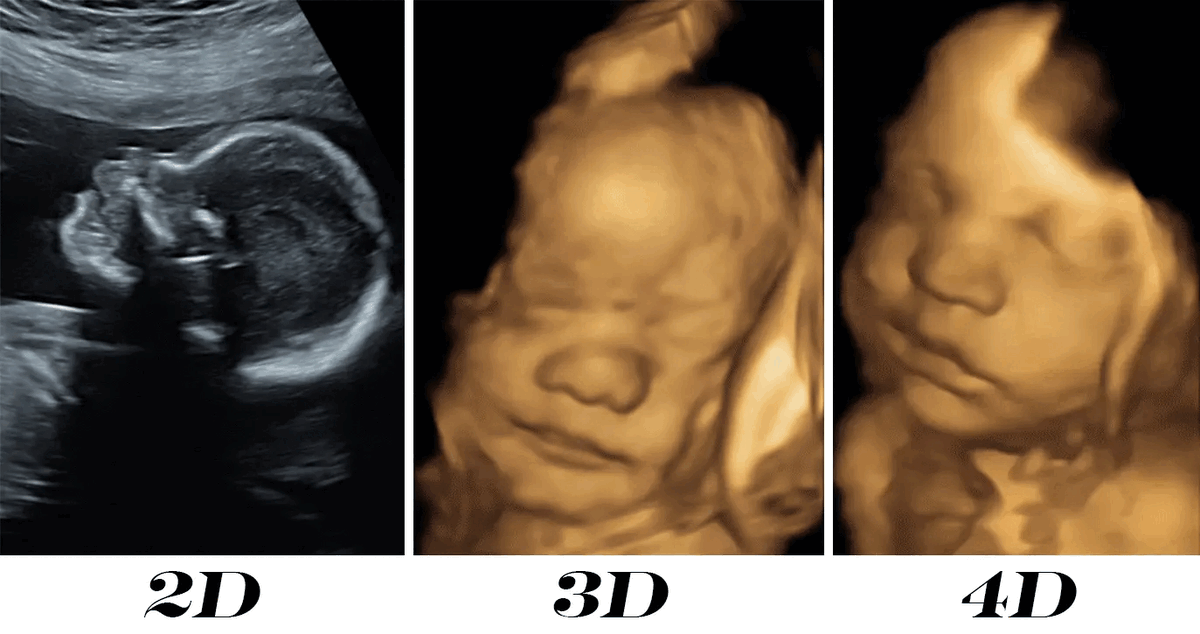

Przykład USG 2D/3D/4D

Opis obrazu